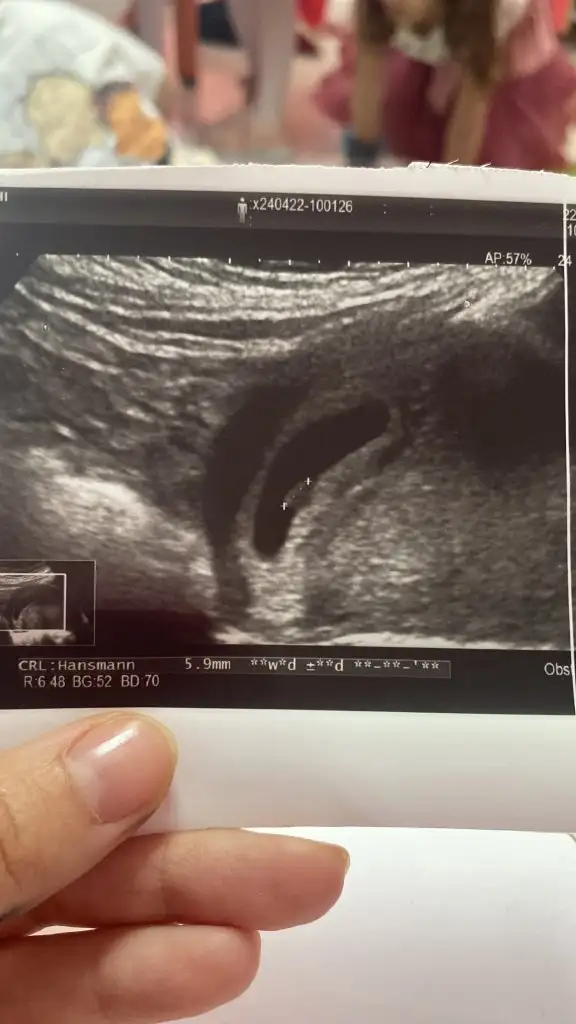

Ben az önce kendi doktoruma gittim. Kesenin etrafında herhangi bir kanama falan yok dedi. Hatta bebeği gördük kalp atışını da dinletti. 1 hafta yat dinlen dedi. Modunuzu hiç düşürmeyin. Dün benim de bebeği göremediler cihazdan kaynaklı olabilirmişbende 6+1 de gitim .vajinal ultrasonda 12mm kese ve yolk vardi ama bebek yoktu. Endiselendirdi bu beni. Bir hfta bekleyelim dedi.. 4gun sonra gidecegim .. haa birde gorunmedigi gun beta bakti 28.600 cikti fakat iki gun sonra sadece %20 artis olmustu betada. Moodum cok dusuk. İnsallaj ikimizde hayirli haber aliriz .cok arkdasimiz var 7.hftada hem bebekk hem kalp atisi duyan:)

ÇOOOKK SEVİNDİM :) kaç haftalıkken duymuş oldun peki :) peogestan bende kullanıyorum . daha önce kullanmışmıydın progestan ?Kuzum kanama alanım yokmuş hem vajinal hem karından baktıkalp atışınıda duyduk çok mutluyumm

çok sevindimmKızlar merhaba 6+5 kalp atışını duyduk az önce çok şükür kucağımıza sağ salim alalım hepimiz![]()

Karından baksakta duyulur muhtemelen ama vajinal bakalım garanti olsun dedi vajinal baktıçok sevindimmkarından mı vajinamı? bende cuma günü gideceğim tam 6+5 olmuş olacak . umarım bende duyarım